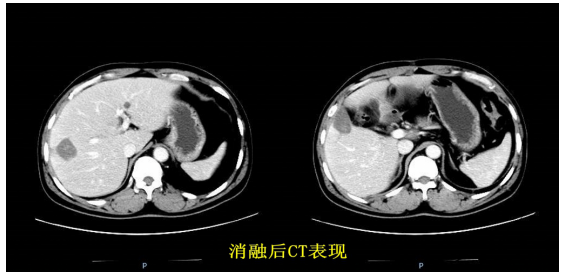

病例2:男,65岁,因“肝脏占位性介入治疗后返院复查”,CT提示:肝Ⅲ、Ⅴ、Ⅵ段占位,考虑原发性肝癌。

病例特点:患者肝Ⅴ、Ⅵ段肿瘤靠近肝脏表面,常规体外消融容易伤及膈肌及腹壁,肝Ⅲ段肿瘤前方贴近腹壁,后方紧挨胃,常规体外消融则会造成腹壁及胃的损伤。